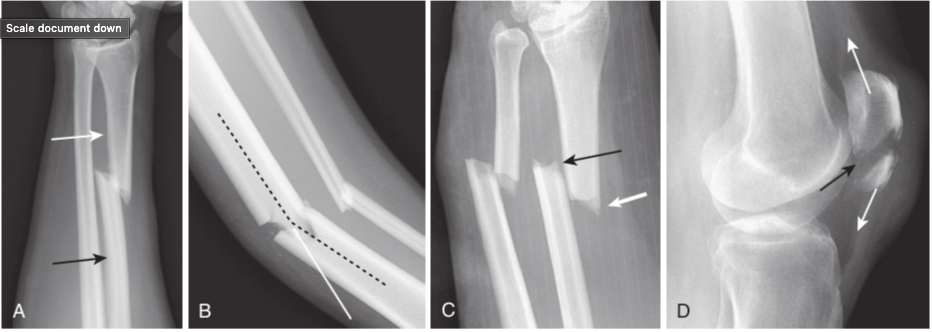

Fracture parameters.

The orientation of fracture fragments is described by using these four parameters. A,Displacement describes the amount by which the distal fragment (white arrow)is offset, front-to-back and side-to-side, from the proximal fragment (black arrow). B,Angulation describes the angle between the distal and proximal fragments (dotted black line)as a function of the degree to which the distal fragment is deviated from its normal position (solid white line). C,Shortening describes how much, if any, overlap occurs at the ends of the fracture fragments (white and black arrows). The opposite term from shortening is distraction(D),which refers to the distance the bone fragments are separated from each other (two white arrows show pull of tendons on fracture fragments of patella; black arrow points to distraction of fracture).

Rotation.

An unusual abnormality in fracture positioning, almost always involving the long bones, which describes the orientation of the joint at one end of the fractured bone relative to the orientation of the joint at the other end of the fractured bone. To appreciate rotation, both the joint above and the joint below a fracture must be visualized, preferably on the same radiograph. In this patient, the proximal tibia (black arrow)is oriented in the frontal plane, and the distal tibia and ankle (white arrow)are rotated and oriented laterally.